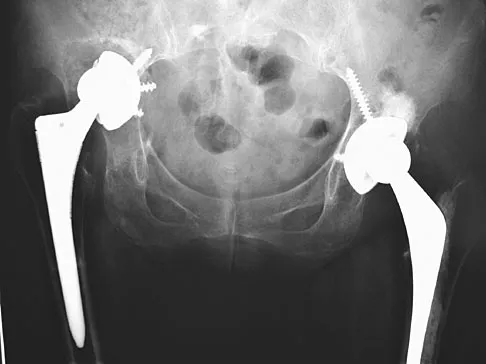

Figures 40a and 40b show the pre- and postoperative radiographs of an 82-year-old woman with bilateral hip pain who has had staged total hip arthroplasties. To minimize potential injury to the sciatic nerve at the time of surgery, the surgeon should

To improve hip biomechanics and secure more suitable bone for acetabular fixation, the true acetabulum is often resurfaced in patients who have developmental dysplasia of the hip, thus lowering the hip center and lengthening the leg. Acute lengthening of more than 3 cm will place excessive tension on the sciatic nerve and require a femoral shortening to avoid sciatic nerve injury. The other maneuvers will not relieve sciatic nerve tension because of limb lengthening. Koval KJ (ed): Orthopaedic Knowledge Update 7. Rosemont, IL, American Academy of Orthopaedic Surgeons, 2002, pp 430-431.